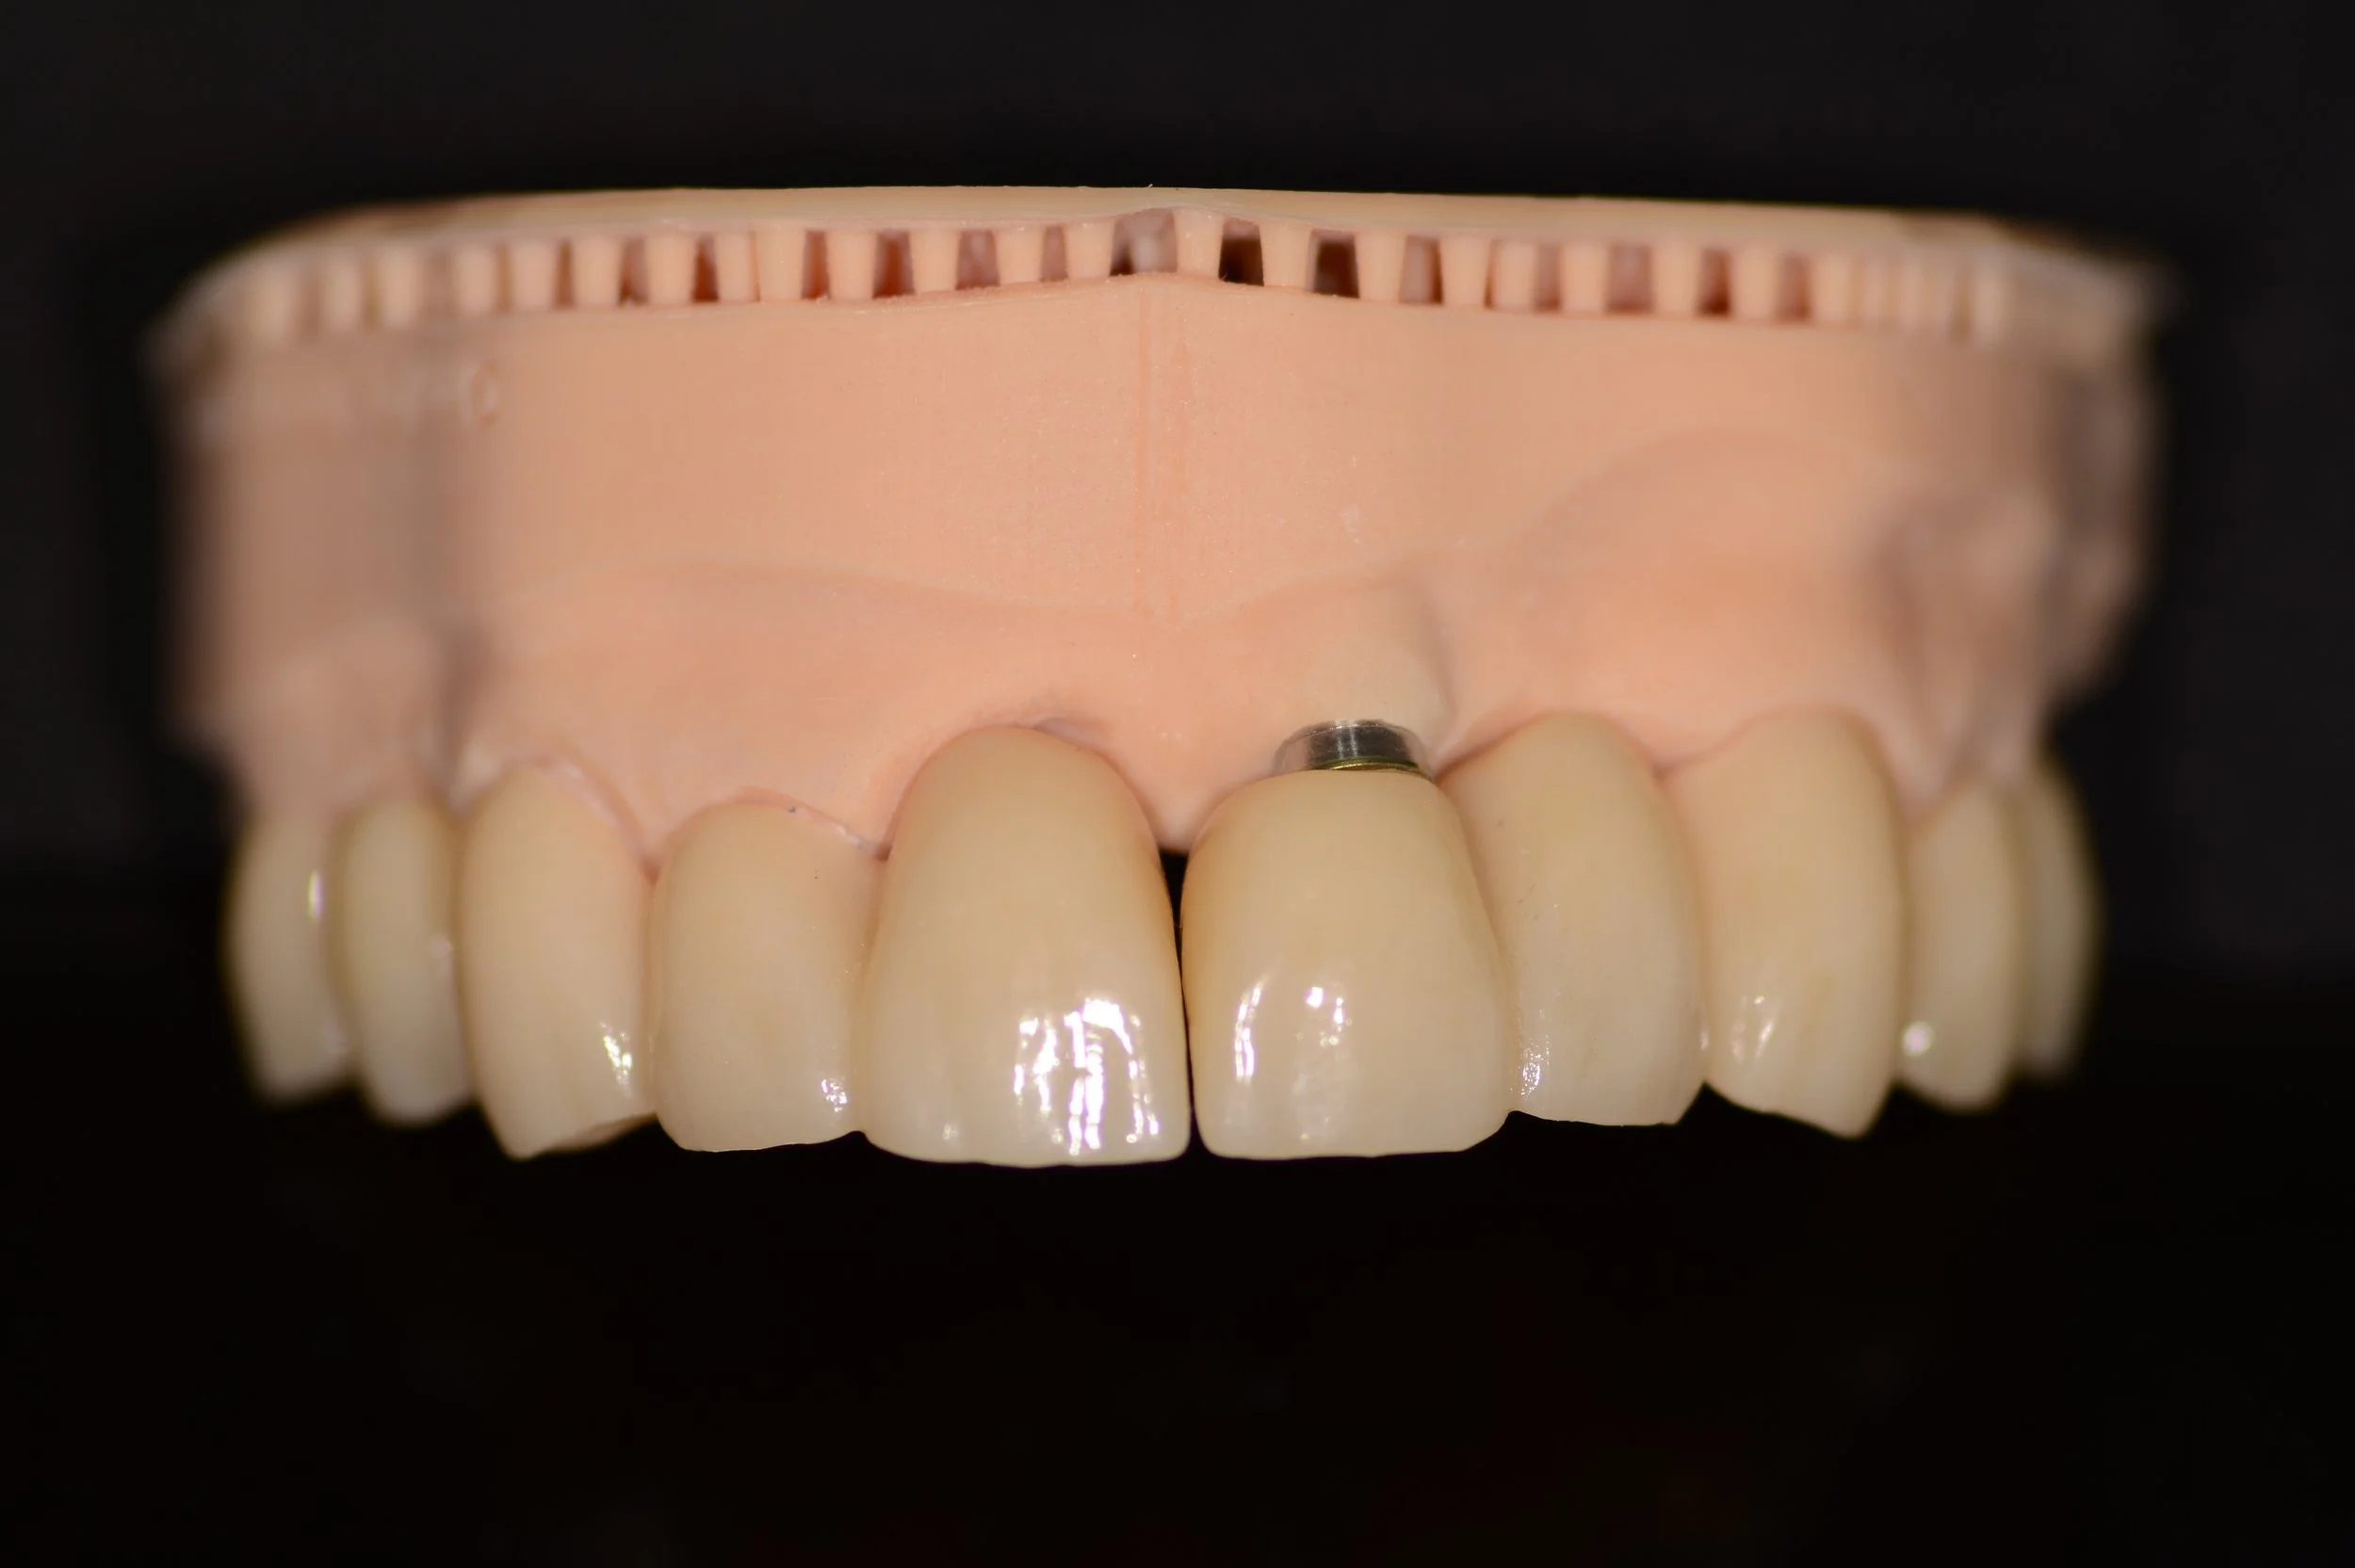

Después

RESULTADO FINAL: El paciente quedó conforme con el tratamiento, recuperó su salud, confort y estética.